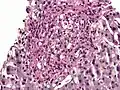

PAS diastase showing Histoplasma in a liver biopsy.

Periodic acid–Schiff–diastase (PAS-D, PAS diastase) stain is a periodic acid–Schiff (PAS) stain used in combination with diastase, an enzyme that breaks down glycogen. PAS-D is a stain often used by pathologists as an ancillary study in making a histologic diagnosis on paraffin-embedded tissue specimens. PAS stain typically gives a magenta color in the presence of glycogen. When PAS and diastase are used together, a light pink color replaces the deep magenta. Differences in the intensities of the two stains (PAS and PAS-D) can be attributed to different glycogen concentrations and can be used to semiquantify glycogen in samples. In practice, the tissue is deparaffinized, the diastase incubates, and the PAS stain is applied.

An example of PAS-D in use is in showing gastric/duodenal metaplasia in duodenal adenomas.[1] PAS diastase stain is also used to identify alpha-1 antitrypsin globules in hepatocytes, which is a characteristic finding of alpha-1 antitrypsin deficiency.[2] PAS diastase stain is also used in diagnosing Whipple’s disease, as the foamy macrophages that infiltrate the lamina propria of the small intestine in this disease possess PAS-positive, diastase-resistant inclusions.[3]